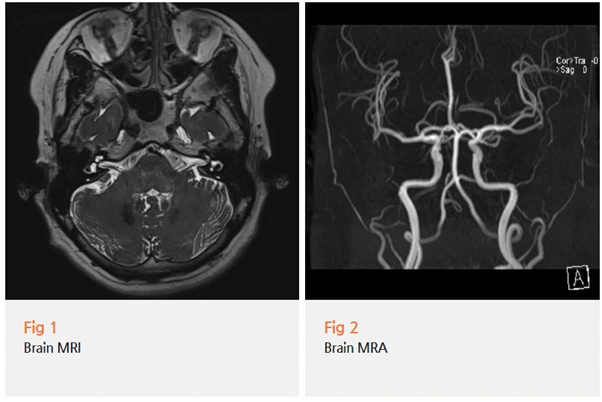

그런데 진단 과정에서 한 가지 더 중요한 것을 발견했어요.

환자분은 잇몸 통증 외에도 두통과 목 통증을 함께 호소하고 계셨어요.

처음에는 각각 별개의 증상처럼 보였지만,

저는 이 두 가지가 연결되어 있을 가능성을 염두에 뒀습니다.

경추 디스크나 일자목으로 인해 상부 경추 주변 근육이 긴장되고 후두신경이 과도하게 흥분하면,

이 자극이 삼차신경 핵으로 전달되어 안면부 통증을 유발하거나 악화시킬 수 있어요.

이를 삼차경추복합체와 관련된 신경학적 연관성이라고 설명할 수 있는데요.

쉽게 말하면 목의 신경 흥분이 얼굴 통증으로 이어지는 메커니즘이에요.

이 환자분의 경우, 경추 상태를 함께 평가했을 때

실제로 경추 디스크와 목 근육 긴장 소견이 동반되어 있었습니다.

그래서 저는 삼차신경통에 대한 약물치료만 진행하지 않고,

경추에 대한 치료를 병행하는 방향으로 계획을 세웠어요.